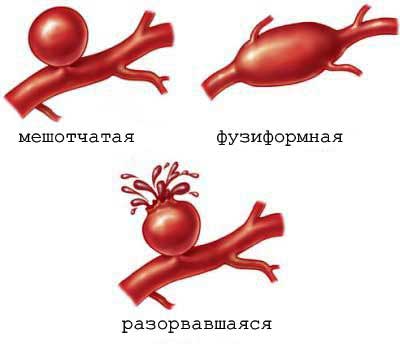

Когда речь заходит о клипировании аневризмы, подразумевается процедура, направленная на изоляцию аневризмы от общего кровообращения. Это достигается путем установки специальной клипсы на шейку пораженного сосуда.

Клипирование аневризмы сосудов — это хирургическая процедура, направленная на предотвращение разрыва аневризмы, что может привести к серьезным осложнениям, включая инсульт или смерть. Врачи отмечают, что данная операция позволяет создать барьер, который изолирует аневризму от кровотока, тем самым снижая риск ее разрыва. Однако, как и любая хирургическая манипуляция, клипирование может иметь последствия. Среди них — возможность повторного появления аневризмы, неврологические нарушения, а также инфекции. Врачи подчеркивают важность тщательной диагностики и индивидуального подхода к каждому пациенту, чтобы минимизировать риски и обеспечить наилучший исход. В целом, при правильном выполнении и соблюдении всех рекомендаций, клипирование аневризмы может значительно улучшить качество жизни пациента и продлить его жизнь.

- аневризма размером 7 мм и более;

Клипирование аневризмы сосудов — это хирургическая процедура, направленная на предотвращение разрыва аневризмы, которая представляет собой расширение стенки сосуда. Многие пациенты и их близкие выражают опасения по поводу последствий этой операции. Некоторые отмечают, что после вмешательства могут возникнуть головные боли, слабость или изменения в когнитивных функциях. Однако большинство людей сообщают о положительном опыте, отмечая, что клипирование помогло избежать более серьезных осложнений, таких как инсульт. Важно, чтобы пациенты обсуждали все возможные риски и преимущества с врачом, чтобы принять обоснованное решение. Поддержка со стороны семьи и друзей также играет ключевую роль в процессе восстановления.

Ухудшение состояния пациента после хирургического вмешательства встречается достаточно редко. Согласно статистике, этот показатель не превышает 10%. Тем не менее, принимая решение о лечении аневризмы, пациенту важно тщательно оценить все возможные риски.

Чаще всего осложнения возникают при разрыве аневризмы до операции или во время самой процедуры.

Если отказаться от лечения, аневризма будет постепенно увеличиваться, что в конечном итоге может привести к ее разрыву и кровоизлиянию, что часто заканчивается летальным исходом.

В группе геморрагических осложнений микрохирургического клипирования аневризм выделены следующие варианты: разрыв аневризмы, отрыв шейки аневризмы от артерии, повреждение крупных венозных стволов с формированием венозного инсульта.